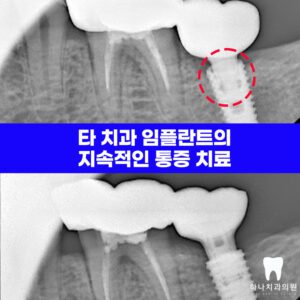

울산치과추천 타 치과 임플란트의 지속적인 통증 치료

울산치과추천 타 치과 임플란트의 지속적인 통증 치료   안녕하세요! 하나치과입니다~:) ​ 임플란트는 1960년대 스웨덴의 정형외과 의사였던 브레네막 교수님에 의해 개념이 도입되고 치과 영역에 조심스럽게 활용되기 시작합니다. ​ 초기에는 치과용 임플란트가 성공률이 증가하고 장기간 유지하면서 성공적으로 기능하는 것을 본 치과 의사들이 믿음을 가지면서 대중화되기 시작하는데요. ​ 이렇게 발전을 거듭해오면서 장점이 있는 더보기…